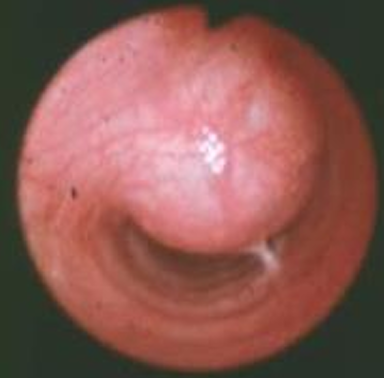

- Diagnosis : Radiography & Tracheoscopy

| Radiography | Tracheoscopy |

![]() | ![]() |